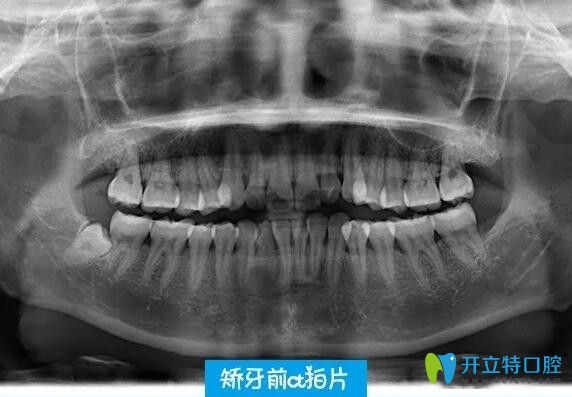

通過牙片,醫(yī)生說我的牙齒只是輕微咬合不正、有些齙牙,這種情況不用拔牙~~~確定了矯正方案,在半個(gè)月后才戴的隱適美隱形牙套~~~